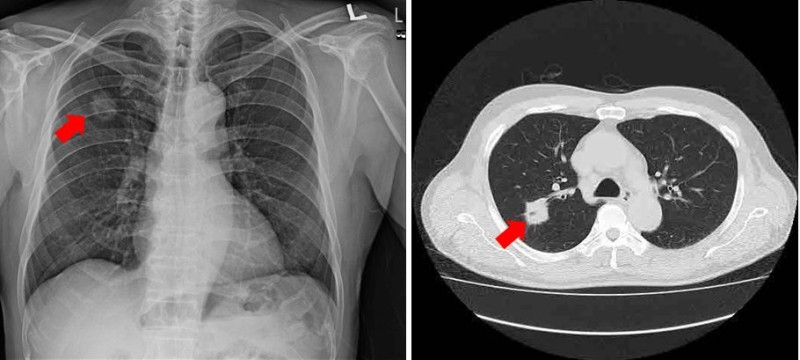

그리고 최소한은 검진이라도 국가에서 해주는 저희가 국가검진이 아주 잘 돼 있다고 하는데, 엑스레이나 저소량 시티 같은 그런 국가검진이라도 꾸준하게 이제 잘 챙겨서 잘 받으시고

어찌 호흡기 증세가 있을 때 빨리 전문가와 만나서 필요한 검사들을 협의하시는게 괜찮을동등합니다.

✔ 초기 증상은 거의 없으나, 기침, 각혈, 가래 변화, 통증, 호흡곤란, 체중 감소 등으로 나타날 수 있습니다.

✔ 증상이 경미하더라도 검진을 통해 조기 발견이 중요하며, 금연과 정기 건강검진이 예방의 핵심입니다.